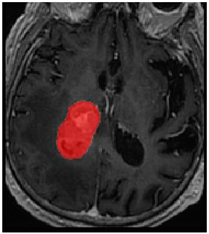

Three cases from the NTUH dataset showing representative results of different models were shown in Table 2, Table 3 and Table 4. The overall dice scores of these networks on the NTUH dataset ranged from 0.33 (DeepMedic) to 0.51 (V-Net). Table 5 shows the detailed performance of each network tested with the NTUH dataset.

Table 2.

Predictions with low dice scores.

Table 3.

Predictions with average dice scores.

Table 4.

Predictions with high dice scores.